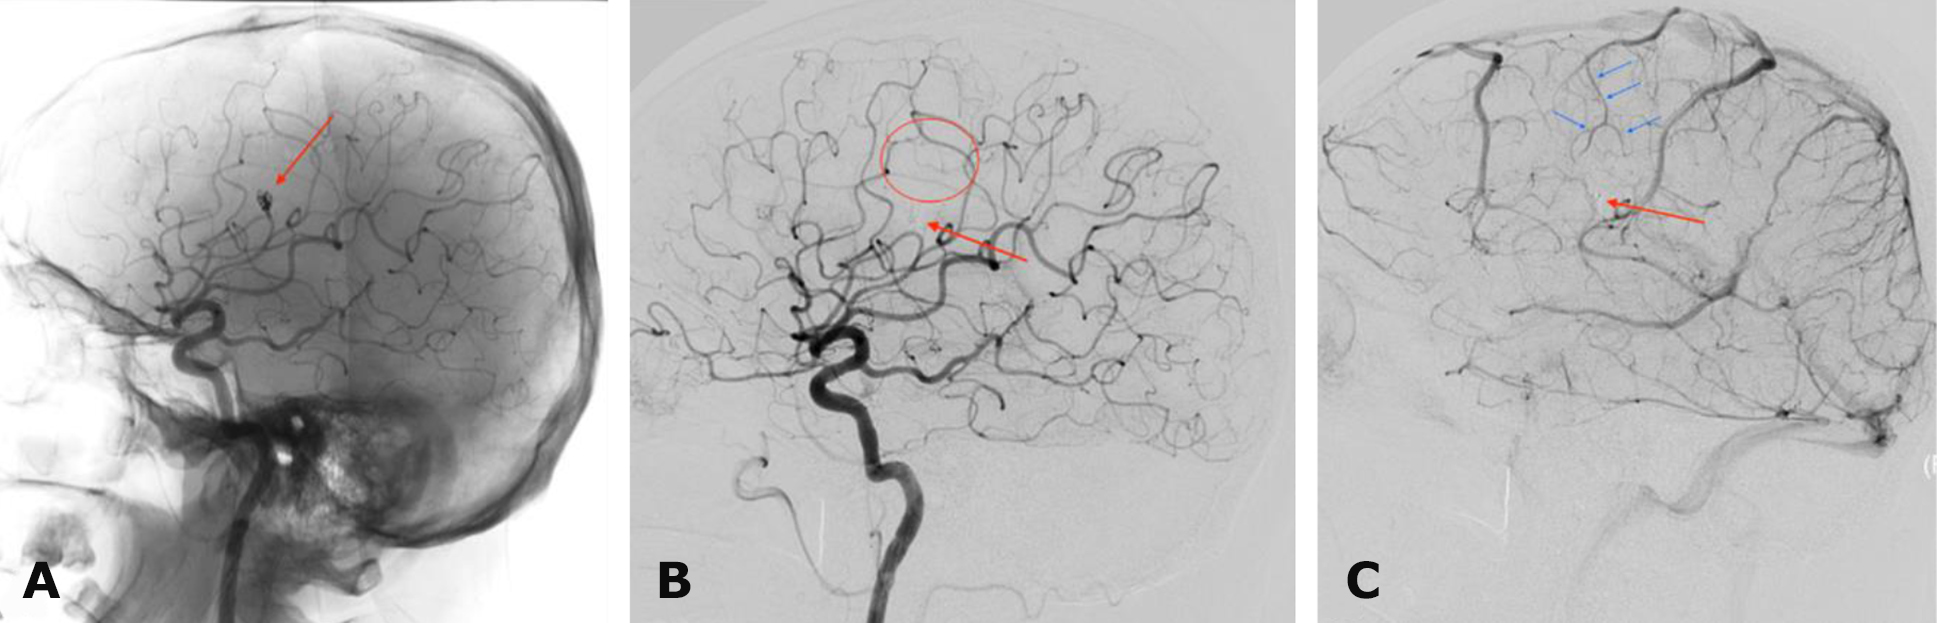

Given the spontaneous onset of symptoms, further diagnostic evaluation was performed using transradial selective digital subtraction cerebral angiography. A mycotic aneurysm of the M4 segment of the right middle cerebral artery was identified (Fig. 6).

Fig. 6. Preoperative cerebral angiography. Right internal carotid artery territory: A – anteroposterior projection, late arterial phase; B – left lateral projection, arterial phase The red arrow indicates a mycotic aneurysm of the M4-segment of the right middle cerebral artery

As a first stage, X-ray endovascular deconstructive embolization of the mycotic aneurysm of the M4-segment of the right middle cerebral artery using detachable microcoils was performed on October 3, 2024 (Fig. 7).

Fig. 7. Postoperative cerebral angiography. Right internal carotid artery territory: A – angiogram in the left lateral projection without digital subtraction; B – subtraction angiogram in the left lateral projection, arterial phase; C – subtraction angiogram in the left lateral projection, late arterial phase. The red arrow indicates the excluded aneurysm of the M4-segment of the right middle cerebral artery; the red circle denotes the avascular area after deconstructive exclusion of the arterial aneurysm; blue arrows indicate compensatory arterial blood flow within the territory of the excluded aneurysm

In the same session, X-ray endovascular embolization of the right MMA using the Onyx™ embolic agent was performed on October 3, 2024 (Fig. 8).

Fig. 8. Postoperative cerebral angiography. Right external carotid artery territory: A – subtraction angiogram in the left lateral projection; B – superselective subtraction angiogram of the MMA in the left lateral projection; C – angiogram in the left lateral projection without digital subtraction. The red arrow indicates the maxillary artery; blue arrows indicate the MMA and its branches; the yellow arrow denotes the contrast-enhanced embolization zone of the MMA; the green arrow indicates microcoils in the projection of the mycotic aneurysm

Follow-up brain MRI was performed 3 months after surgery (Fig. 9). Complete resolution of the chronic subdural hematoma was observed, with restoration of the normal position of the midline brain structures. On T2-weighted images, a focus of ischemic stroke was visualized in the right frontal lobe within the vascular territory of the excluded branch of the right middle cerebral artery together with the aneurysm. At follow-up examination, no focal neurological deficits were present, and headache and dizziness had resolved.

Fig. 9. Postoperative (3-months) brain MRI, T2-weighted images: A, B – axial projections. The red circle indicates a focus of ischemic stroke in the right frontal lobe measuring 19 × 13 mm